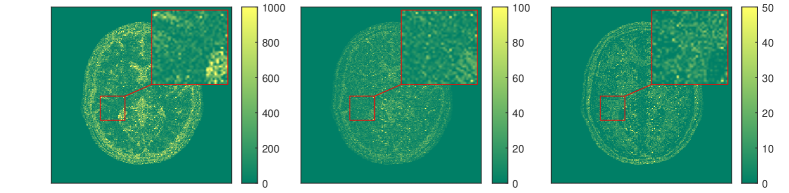

The results for each of the above mentioned algorithms can be found in Figures 3 and 4. We use the MRF reconstruction as initialization for the L-M algorithm, and compare that with the result of the BLIP algorithm when using a relatively refined dictionary. The advantage of integrated-physics approaches is evident by checking the reconstructions in Figure 3 as well as quantitatively by looking at the error maps in Figure 4. In this example, we have used a time series of the 1/8 Cartesian-subsampled k-space data (Fourier coefficients of magnetizations) of length 40. In the original MRF algorithm (typically requiring a large time series of k-space data), this test setting is far from yielding a reasonable result, while BLIP has improved a little by enforcing the projection to the Bloch manifold. But still one observes deficiencies. The method with integrated physics, however, appears to be efficient and it returns the best results among the three methods.

The results in [57] show that the proposed integrated physics model can work well for settings where an explicit solution formula for the Bloch equations is available. However, in most cases (excitation sequences) the Bloch equations have no explicit solution formula. In addition, from a practitioners perspective the Bloch equations appear to be only a simplified mathematical model under some assumptions. As in reality these assumptions are often not realistic, one indeed requires a more complex model. In this vein, deep learning turns out to be a useful data-driven technique for learning or approximating such physical models. In Subsection 3.3 we will therefore discuss extracting physical laws from data.